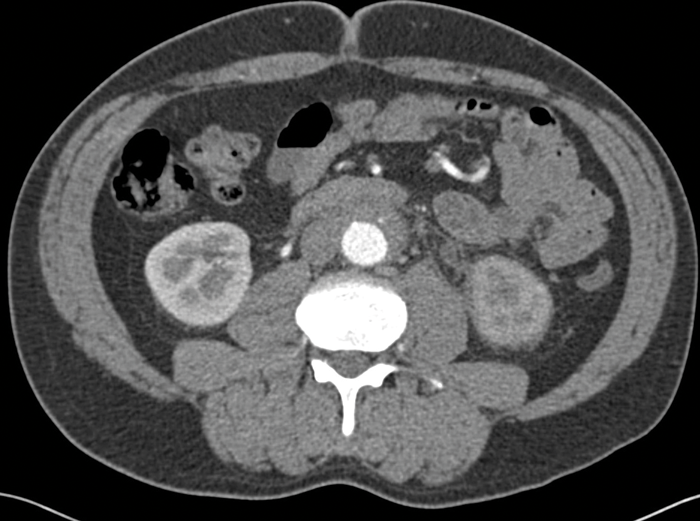

The ureters may be medially deviated due to the fibrotic tissue, rather than laterally deviated as is seen in cases of lymphoma or extensive retroperitoneal lymphadenopathy from other causes. The fibrotic tissue may be seen to extend to encase the common iliac arteries as well as the aorta, depending on the extent of the disease (Figure 3).

Figure 3: Arterial phase CT abdomen shows the soft tissue extending inferiorly to encase the iliac arteries.

There is loss of the fat plane between the fibrotic tissue and the left psoas muscle.